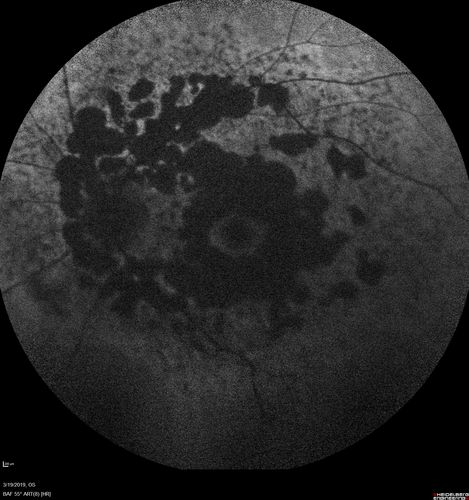

Concentric Geographic Atrophy

76 year old man Gradual vision loss

20/32 OD; 20/40 OS

No medicines, Non-smoker

Working and Driving